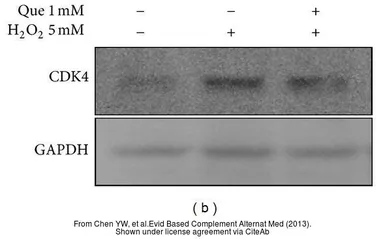

The data was published in the journal Evid Based Complement Alternat Med in 2013. PMID: 24282433

The data was published in the journal Evid Based Complement Alternat Med in 2013. PMID: 23573126

The data was published in the journal Evid Based Complement Alternat Med in 2013. PMID: 23573126